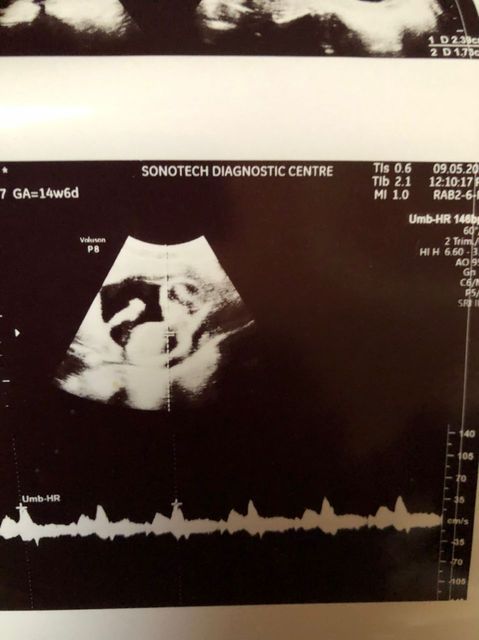

BlogHide Reblurtsreblurtedleifasaur in # blurtafrica • 4 years ago • 5 min readA return to Escape3Points Eco-lodge, now EcovillageAbout 2 months ago I did a post on Escape3points Eco-lodge. This was a post culminating pictures and visits over the last 11 years that I have visited the place during that time a few times. The…dzigbordi in # blurtafrica • 4 years ago • 2 min readWe are having a baby !20 weeks pregnant...reblurtedleifasaur in # blurt • 4 years ago • 1 min readBlurt is down, boo hoo, what to do?Buy Buy Buyreblurtedleifasaur in # hive-196037 • 4 years ago • 1 min readIntroduction to DtubeMy intro to dtube and videos that I will be posting on Blurt, HIVE and on youtube. #dtube #introduction #permaculture #vlog #video #pob #vyb #blurt ▶️ DTubedzigbordi in # blurtafrica • 4 years ago • 2 min readWell wishes to Anas our ukranian friend and all ukrainianswishing my friend the best ....dzigbordi in # blurtafrica • 4 years ago • 2 min readsquid or cuttlefish.....a creature looking like a octopus found on our beach ........reblurtedleifasaur in # blurtafrica • 4 years ago • 1 min readServer_disconnect issue and how to work around itUPDATE as of 23rd February. The issue has been patched now and run through some other servers. Logging in with the keychain should work again on all platforms but things may be a little buggy.…dzigbordi in # blurtafrica • 4 years ago • 3 min readMy valentine surprise day trip.Our valentine day trip to the beer garden and the old fort Good hope.. dzigbordi in # blurtafrica • 4 years ago • 2 min readThe sexy photographyerlearning photography in bikini....dzigbordi in # blurtafrica • 4 years ago • 2 min readFollow up on our wall garden installation.Water plants, mornings and evenings for best result.dzigbordi in # blurtafrica • 4 years ago • 2 min readiPhone photographyiPhone photography for my content creation as a model .dzigbordi in # blurtafrica • 4 years ago • 2 min readGarden wall installationsAt Joon, we plant we construct and we nature.dzigbordi in # blurtafrica • 4 years ago • 2 min readCamping with the boys part 1camping with my husband and his friends.dzigbordi in # blurtafrica • 4 years ago • 2 min readA surprise visit from my girls girlsMy friends came a long way to spend the day with me .dzigbordi in # blurtafrica • 4 years ago • 2 min readMy husband learnt to help keep my 4c hair.My husband ,My 4c hair stylistdzigbordi in # blurtafrica • 4 years ago • 2 min readBackstage of my first international fashion showBackstage ready to hit the runway rocking my makeup by Mac cosmetics.dzigbordi in # blurtafrica • 4 years ago • 1 min readBeach BumI have learnt a long time to accept my body ,because I love myself and the greatest love of all is loving oneself.dzigbordi in # blurtafrica • 4 years ago • 1 min readModel on dutyThe brilliant colors from this top brings out the beauty of melanin, what is your take on thatdzigbordi in # blurtafrica • 4 years ago • 1 min readThe hot comeback........Here I am enjoying some sunlight and relaxing after I fell from my favorite childhood gymnastic pose.dzigbordi in # ibc • 5 years ago • 1 min readIBCcosmos1z8sxl4p2cpsry3jtjmdhr2ef5scn3ztzmucjel